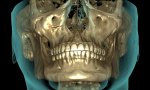

Мой рот изнутри

Я тут какую-то гигапломбу нашёл. чзх